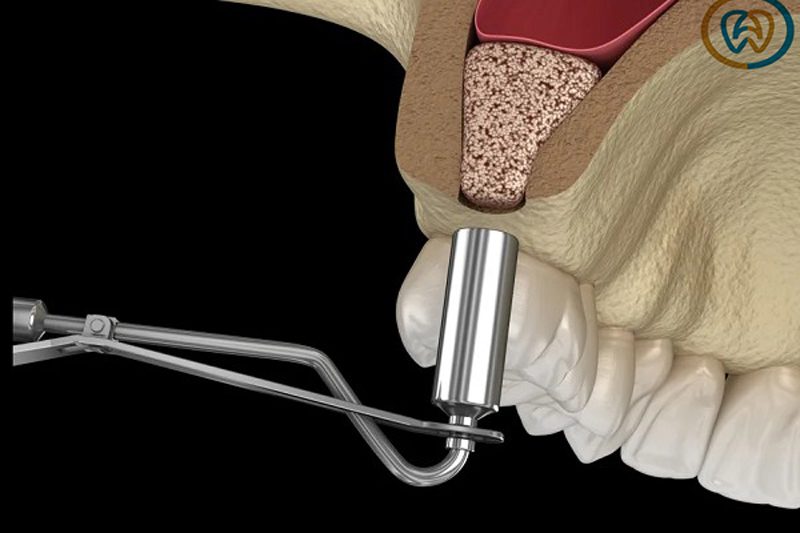

2) سینوس لیفت بسته

اگر تراکم استخوان به اندازه کافی نباشد، احتمال شکست پروسه کاشت ایمپلنت وجود دارد. به عبارتی عمل لیفت سینوس بسته با توجه به میزان آتروفی استخوان و موقعیت بافت استخوانی انجام می شود.

جراحی سینوس لیفت برای ایمپلنت به صورت بسته با هدف بالا بردن سینوس ماگزیلاری و پر کردن شکاف با مواد لازم پیوند استخوان انجام می شود. این پروسه به تشکیل بافت استخوانی کمک زیادی می کند.

هنگامی که استخوان دندان حجم خود را از دست می دهد، کاشت ایمپلنت امکان پذیر نیست. اگر بافت استخوانی دارای فضای کافی نباشد، امکان شکست پروسه ایمپلنت نیز وجود دارد. به همین منظور، عمل سینوس لیفت بسته باید قبل از کاشت دندان انجام شود.

معایب لیفت سینوس بسته

با وجود مزایای متعدد لیفت سینوس بسته، این روش یک عیب بالقوه نیز دارد: محدودیت در مشاهده ساختارهای پشت فک. این محدودیت دید، احتمال پارگی غشای سینوس توسط جراح را افزایش میدهد. پارگی غشای سینوس، منجر به شکست عمل و نیاز به تکرار آن در آینده خواهد شد.